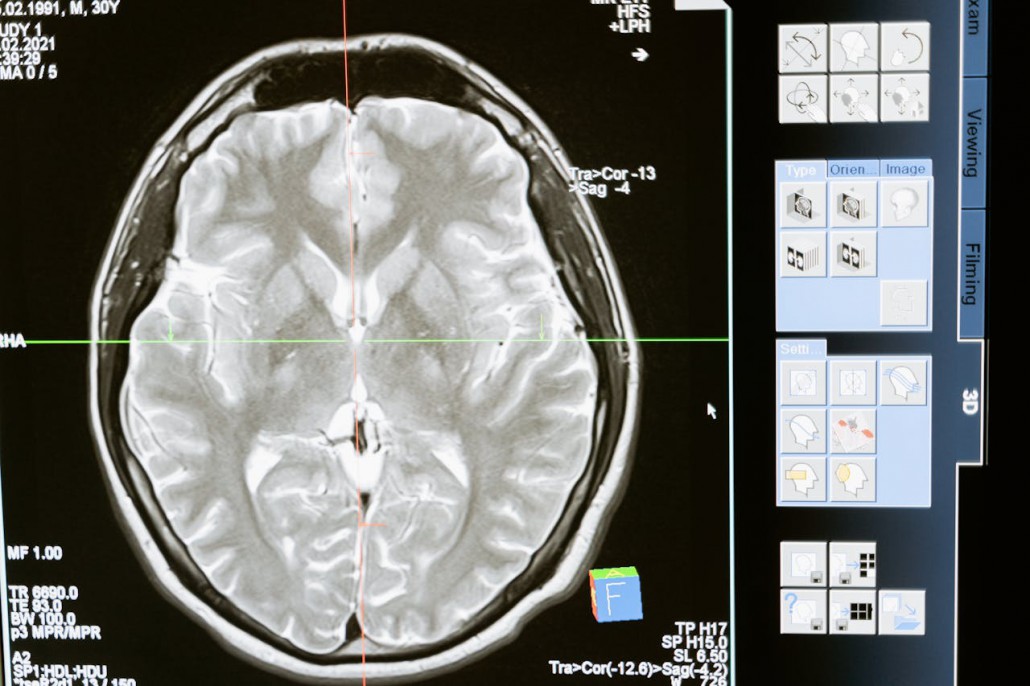

אבצס במוח הינו מצב נדיר ומסוכן מאוד שנוצר עקב זיהום ברקמות במוח. במצב זה נוצרת למעשה מורסה בתוך המוח והיא מכילה מוגלה, חיידקים ותאים של המערכת החיסונית של הגוף. המורסה נמצאת בממברנה נפרדת מרקמות המוח, וחשוב מאוד לאבחן אותה במהירות, באמצעות בדיקת CT או בדיקת MRI – שכן המורסה עלולה לגרום נזק מוחי ואף להוביל למוות.

אבחון מורסה במוח מבוסס על בדיקת דם, שמזהה הימצאות חיידקים מזהמים, ובנוסף נדרש שימוש באמצעי דימות מתקדמים – בדיקת CT או בדיקת MRI – כדי לזהות את מיקומה המדויק של המורסה ואת גודלה. נתונים אלה קריטיים להחלטה כיצד לטפל באבצס ועל כן חשוב מאוד שפענוח ממצאי ה-MRI או ה-CT ייעשה על-ידי אנשי מקצוע מנוסים ומיומנים במיוחד.

כאמור בימינו ישנם טיפולים אפקטיביים מאוד באבצס במוח, ובפרט אחרי אבחון מהיר ומדויק באמצעות בדיקת CT או בדיקת MRI ופענוח מקצועי של הממצאים.